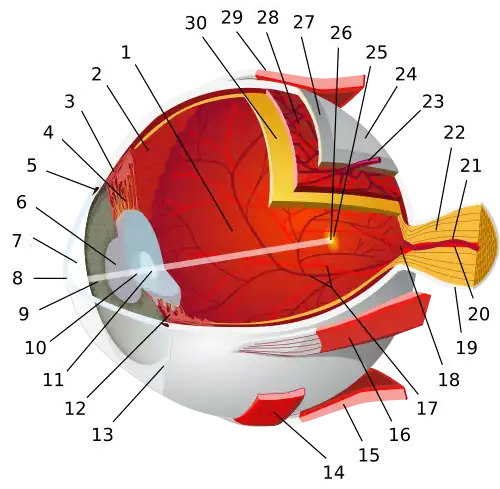

The pupil is the central opening of the iris on the inside of the eye, which normally appears black. The grey/blue or brown area surrounding the pupil is the iris. The white outer area of the eye is the sclera. The central outermost transparent colorless part of the eye (through which we can see the iris and pupil) is the cornea. | |

Cross-section of the human eye, showing the position of the pupil. | |